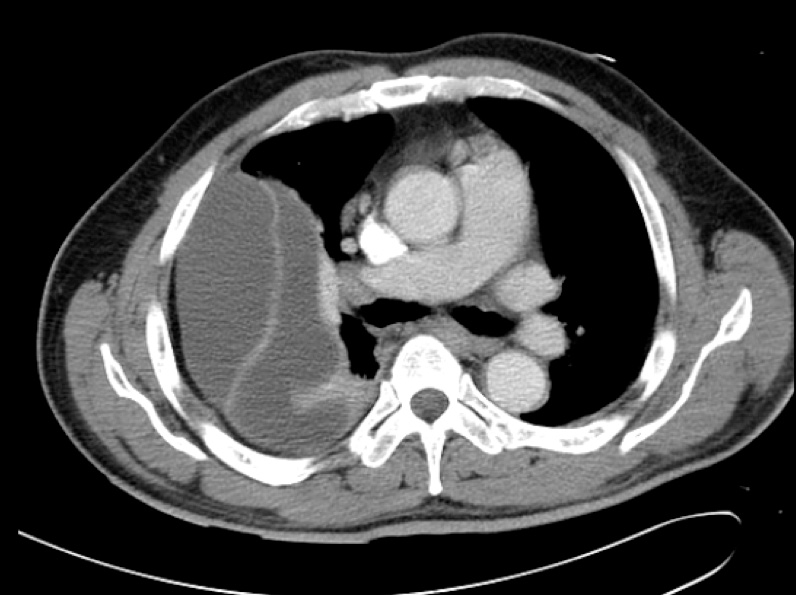

The chest X-ray and subsequent representative CT thorax images are given below, showing a massive right-sided pleural effusion that is also multi-loculated..